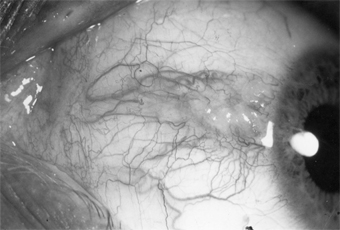

Figure 5-22

Figure 5-22: Pterygium encroaching on the cornea.

A pterygium is a fleshy, triangular encroachment of a pinguecula onto the cornea, usually on the nasal side bilaterally (Figure 5-22). It is thought to be an irritative phenomenon due to ultraviolet light, drying, and windy environments, since it is common in persons who spend much of their lives out of doors in sunny, dusty, or sandy, windblown surroundings. The pathologic findings in the conjunctiva are the same as those of pinguecula. In the cornea, there is replacement of Bowman's layer by hyaline and elastic tissue.